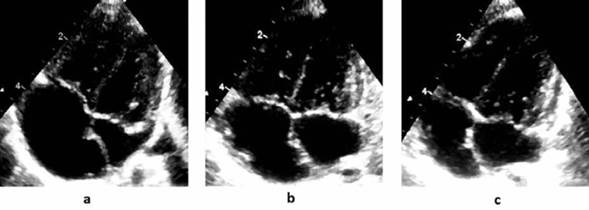

En ambos la aurícula izquierda era pequeña en el período preoperatorio y alcanzó valores de normalidad a los 60 días del posoperatorio (Figura 1). Dicho fenómeno ocurrió en forma rápida y ello aleja la posibilidad que sea consecuencia del crecimiento somático exclu sivamente.

Figura 1: Evolución ecográfica del tamaño auricular corte 4 cámaras caso 2. (a) preoperatorio; (b) 30 días posoperatorio; (c) 60 días posoperatorio.